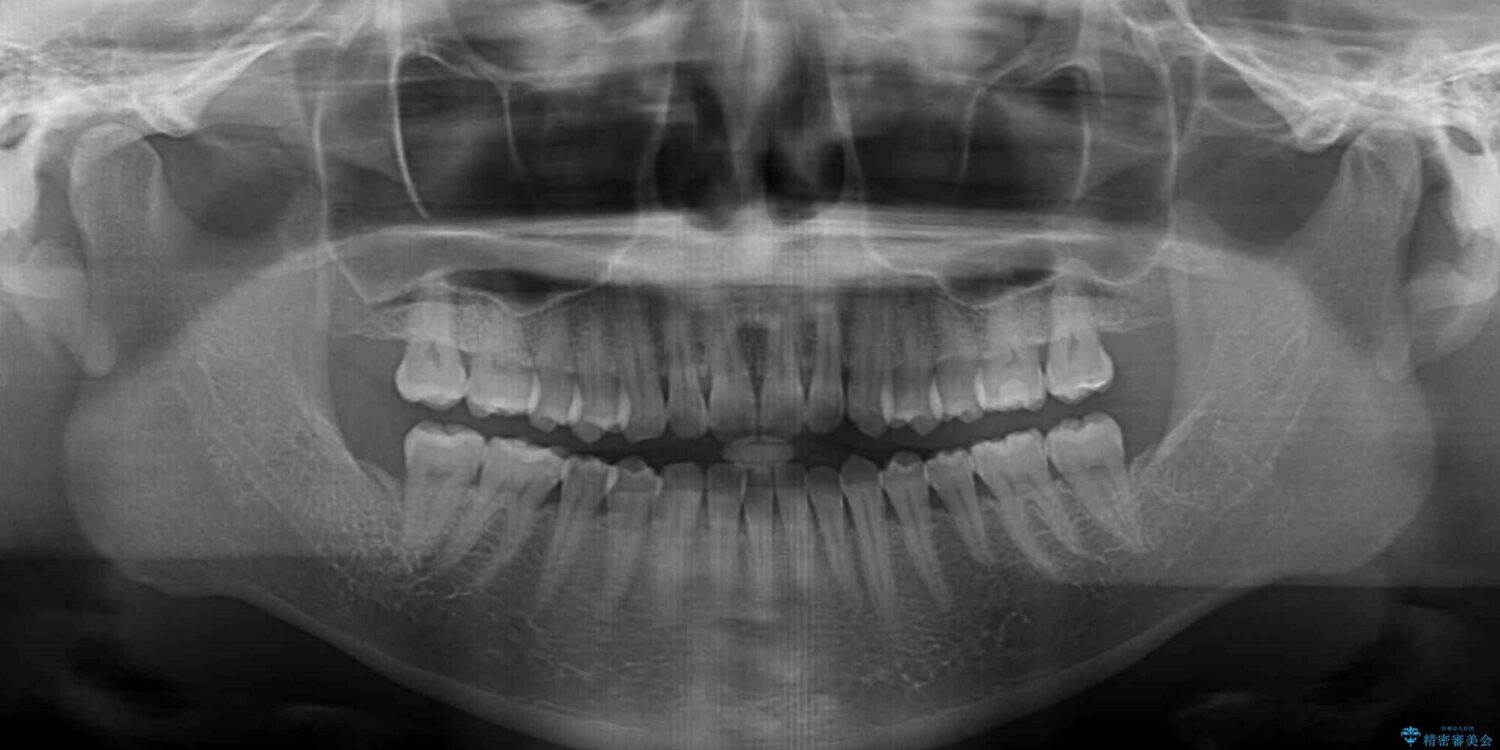

上顎前歯が捻れて前方に飛び出しており、下顎前歯もそれに沿うようにデコボコとなっていました。

IPR(歯と歯の間を削る処置)によりスペースを獲得して上下顎前歯のデコボコを改善し、飛び出している前歯が引っ込むように設定し、インビザラインにて矯正治療を行うこととしました。

装着時間を守ってくださったので、予定通りの期間で終えることができました。インビザライン特有の、奥歯の咬み合わせの問題もなく、しっかりと歯列を改善することができました。